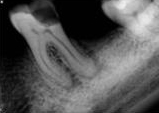

antes depois